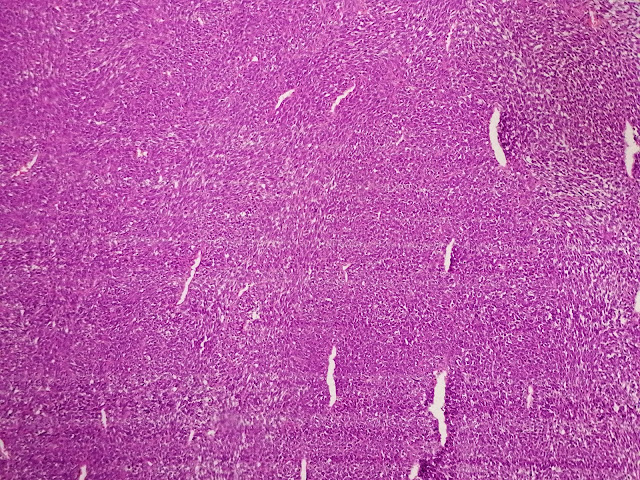

Los cortes histológicos mostraron una neoplasia mesenquimatosa, constituida por células fusiformes monomorfas, de núcleos alargados u ovoides, de cromatina gruesa, y con citoplasma eosinófilo, que en determinadas áreas adoptan un patrón de crecimiento hemagiopericitoide. La lesión neoplásica mostró una actividad mitótica de entre 6 a 7 por 10 campos de alto poder. La neoplasia alternaba con áreas de necrosis y hemorragia. No se identificó invasión linfovascular o perineural. Los bordes de resección estuvieron libres de lesión.

El SS monofásico se caracteriza por presentar células tumorales fusiformes monótonas, con núcleos sobrepuestos, vesiculosos, hinchados, con pequeños nucléolos y citoplasma eosinófilo claro, y presencia de vasos sanguíneos hemangiopericíticos.

En resumen, presentamos un caso de sarcoma sinovial monofásico caracterizado por tener células fusiformes cortas y células redondas monótonas, con vasos hemangiopericíticos, extensas áreas de necrosis tumoral y hemorragia, actividad mitótica frecuente (6 a 7 x 10 campos microscópicos de mayor aumento) por lo que fue catalogado como un sarcoma agresivo de rápido crecimiento. Por lo su relativa frecuencia, hay que tenerlo en cuenta como diagnóstico diferencial al momento de abordar un sarcoma fusocelular. Los estudios de inmunohistoquímica y biología molecular (en caso de estar disponibles) son de fundamental importancia para establecer el diagnóstico en estos casos. En cuanto a la evolución, la paciente se recuperó favorablemente después de la cirugía y fue referida al hospital de especialidad para tratamiento complementario con radioterapia.